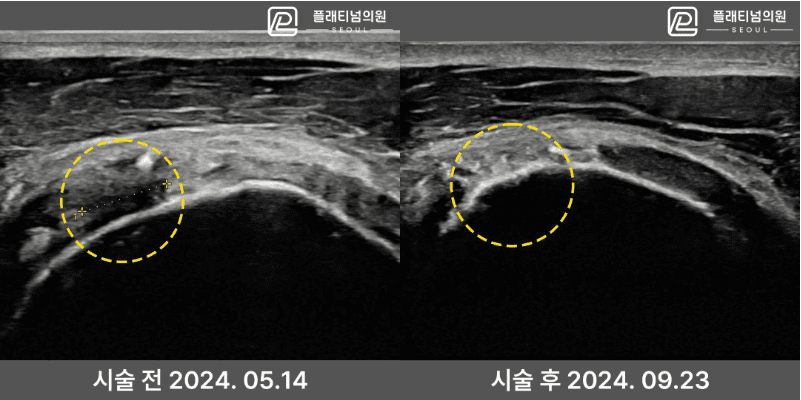

Before & After Ultrasound

Real patient ultrasound comparison. Ligament tissue that showed a defect before treatment is seen recovering after the procedure.

* Individual results may vary. Results are not guaranteed to be identical for all patients.